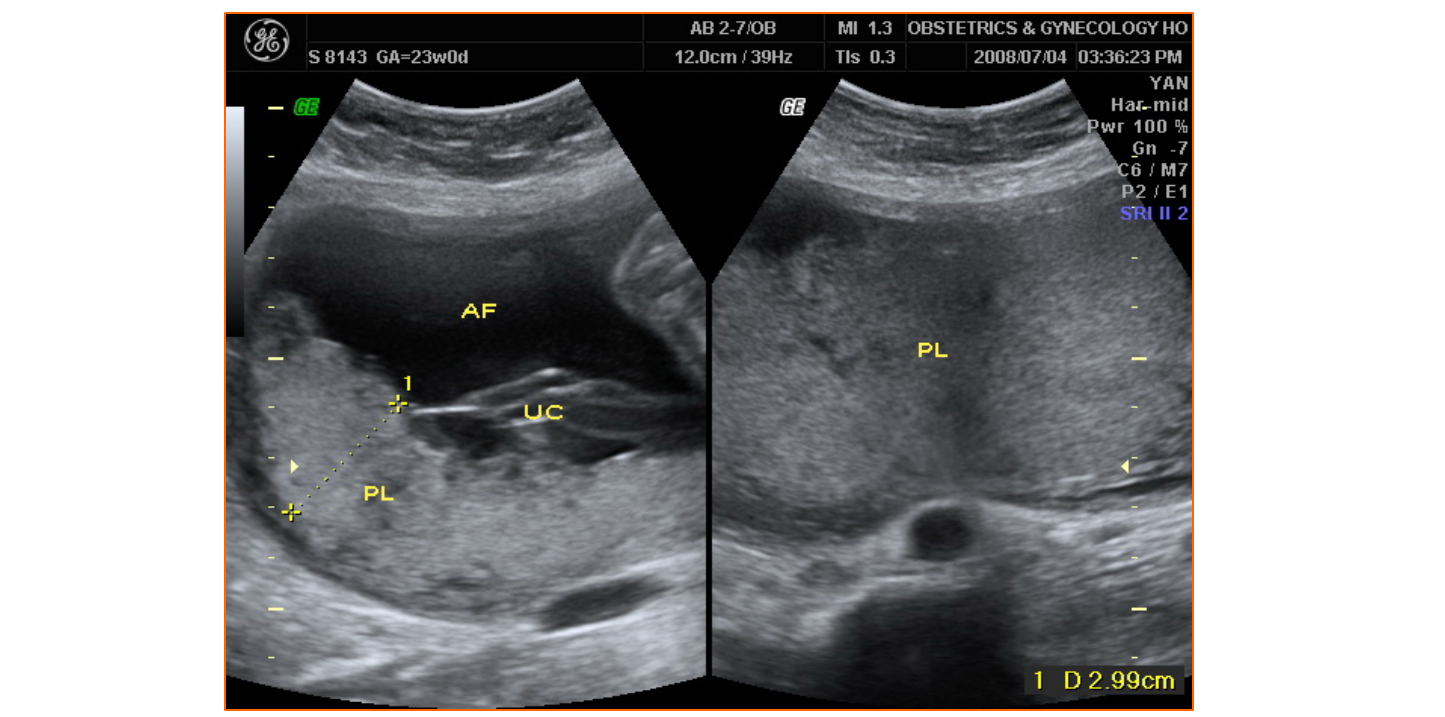

正常中晚期妊娠声像图

• 4.4 异常妊娠声像图